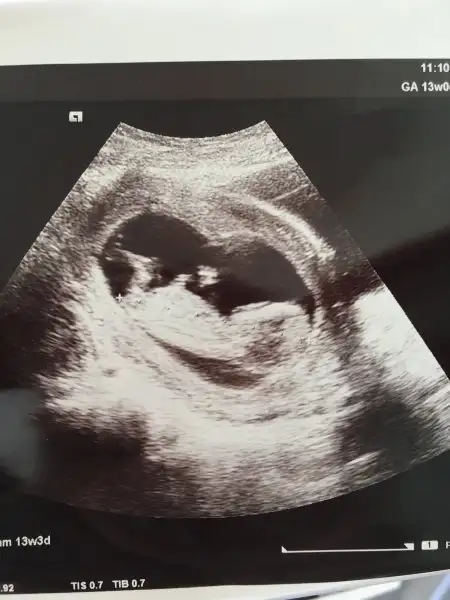

%60 erkek diyorum:)Bu da benim ki 13+3 resmimiz

Ayy bende kıza benzettim bakalım bir daha ki sefer göstercekmi sıpam%60 erkek diyorum:)